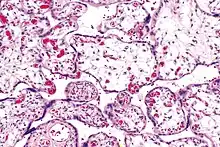

Micrograph of villous immaturity. H&E stain. | |

Placental villous immaturity is chorionic villous development that is inappropriate for the gestational age.

Immature chorionic villi are larger and have more central blood vessels; thus, the diffusion distance for gas and nutrient exchange is larger and, therefore, placental function is impaired.

- Low mag.